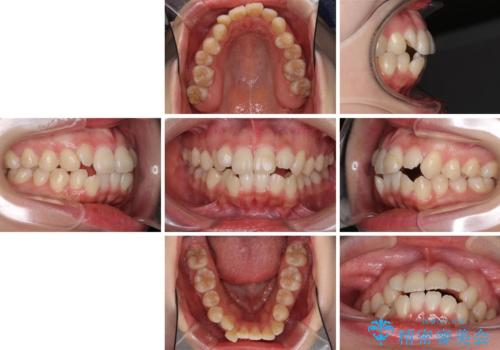

- 口元の突出感を気にして来院された患者様です。

診断の結果、上顎左右第一小臼歯4本抜歯により、叢生を解消するとともに口元を引っ込めていくことが望ましいと判断しました。

抜歯矯正による口元の改善にはワイヤー矯正が望ましいのですが、ダンサーとしての仕事を行っているため、インビザラインにて治療を行うこととしました。

インビザラインによる矯正治療は、どれだけマウスピースを外す時間を短くできるかが成功の鍵となりますが、抜歯矯正ではよりシビアに要求されます。

こちらの患者様は、1日22時間以上を厳守してくださり、3年強で終えることができました。